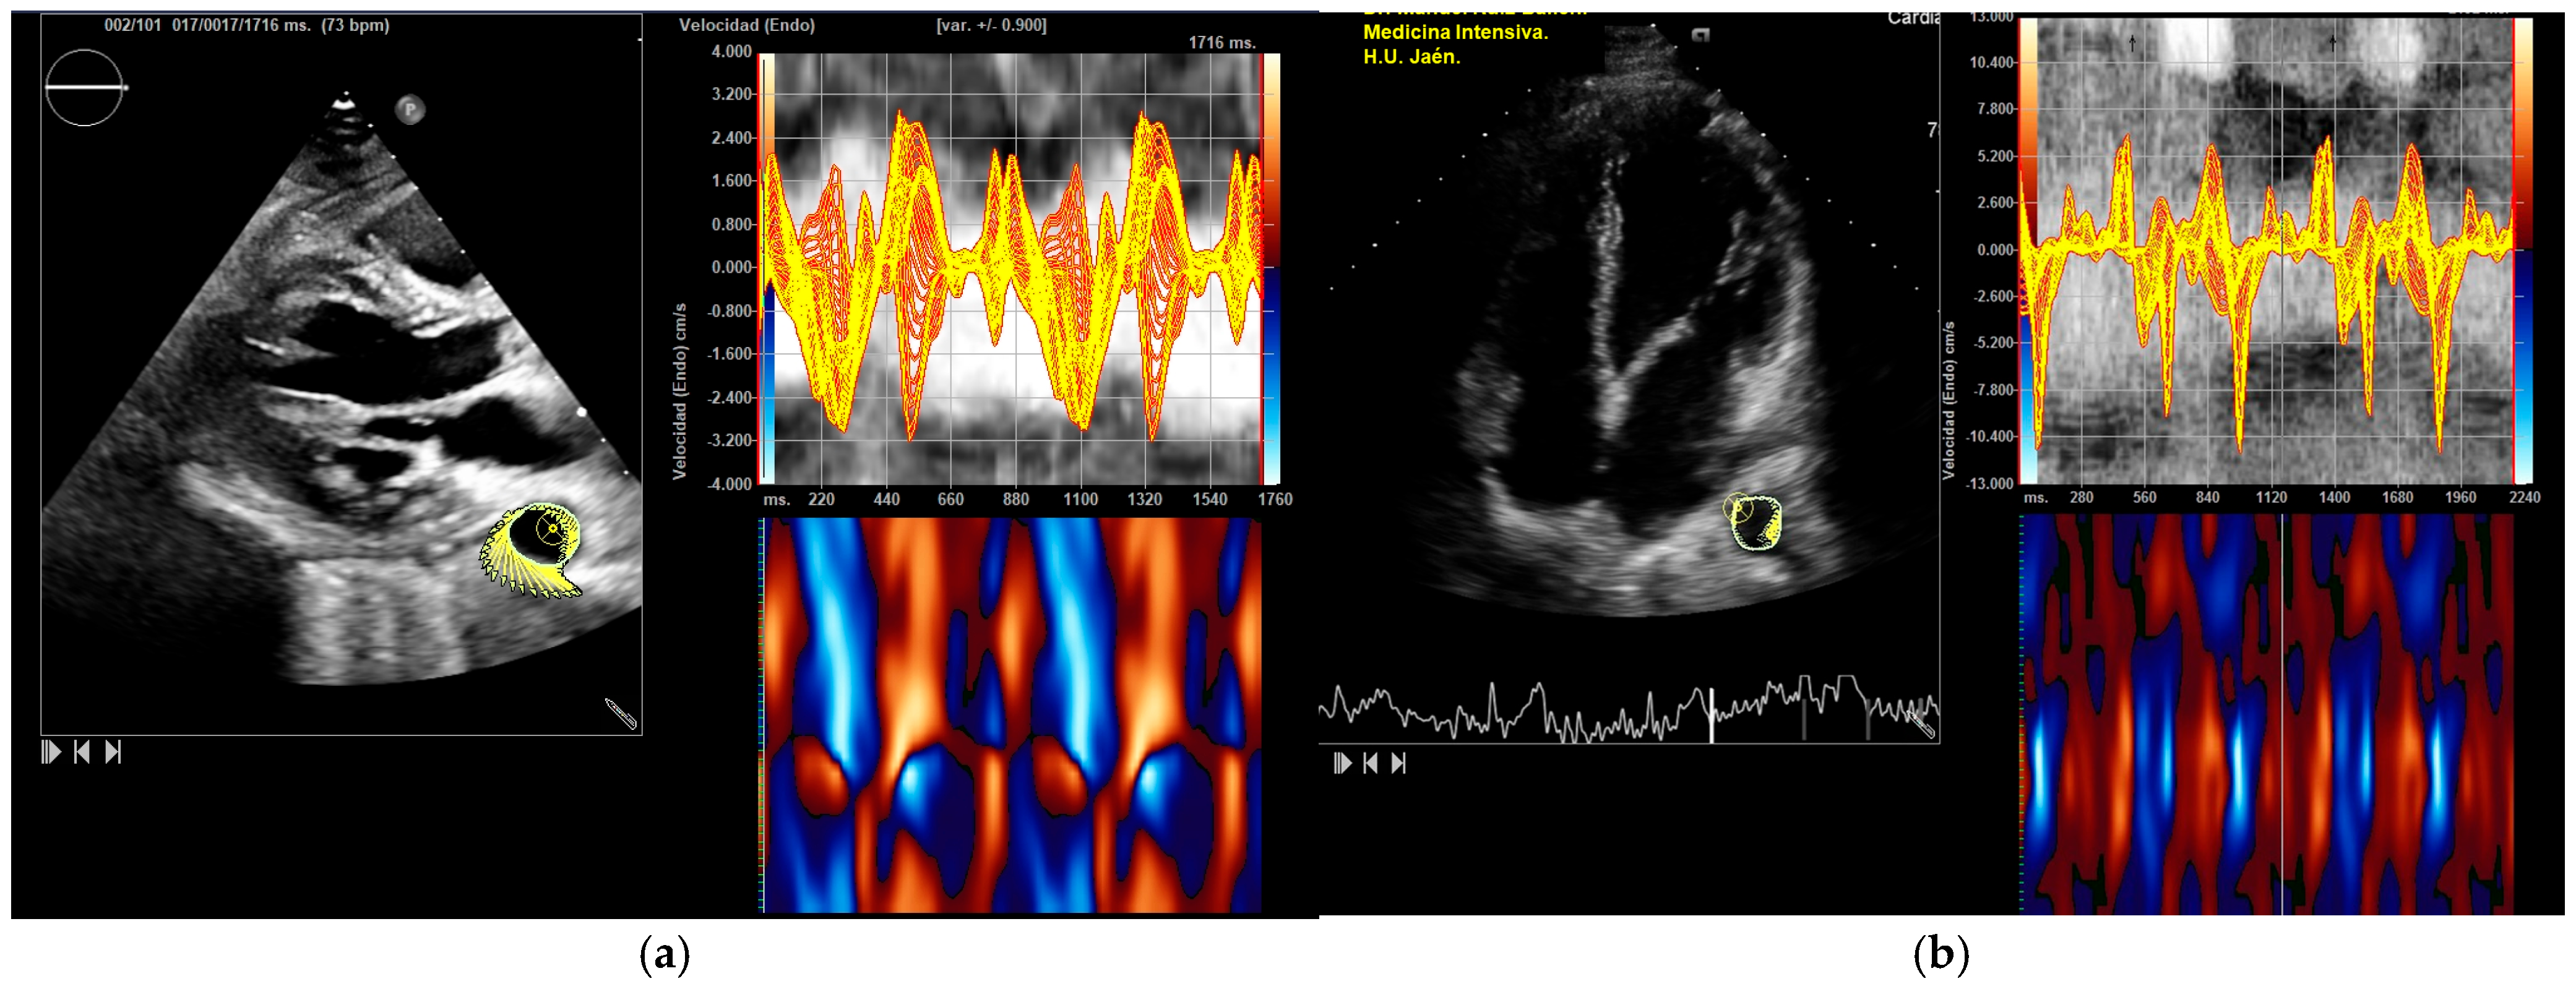

- Ruiz-Bailén, M.; Hidalgo-Martín, J.; Manetsberger, J.; Clau-Terré, F.; Martínez-Gámez, J.; Dagomar Lohman, J.; Lavilla-Lerma, M.L.; Matallana-Zapata, D.F.; Ballesteros-Barroso, M.; Rivera-Fernández, R.; et al. Usefulness of vector velocity imaging in the descending thoracic aorta. Med. Intensiv. Engl. Ed. 2025, 502224. [Google Scholar] [CrossRef]